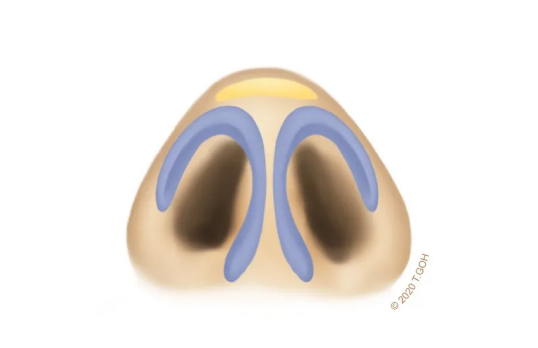

Ideal Triangle and Tip-Defining Points

Similar to the golden ratios of beauty, the nasal tip should form a harmonious triangle with the precise tip-defining points to create the ideal nose.

Explaining the ANATOMY + CARTILAGE GRAFT + SUTURE TECHINQUE for natural tip-plasty

Ideal Triangle and Tip-Defining Points

Similar to the golden ratios of beauty, the nasal tip should form a harmonious triangle with the precise tip-defining points to create the ideal nose.